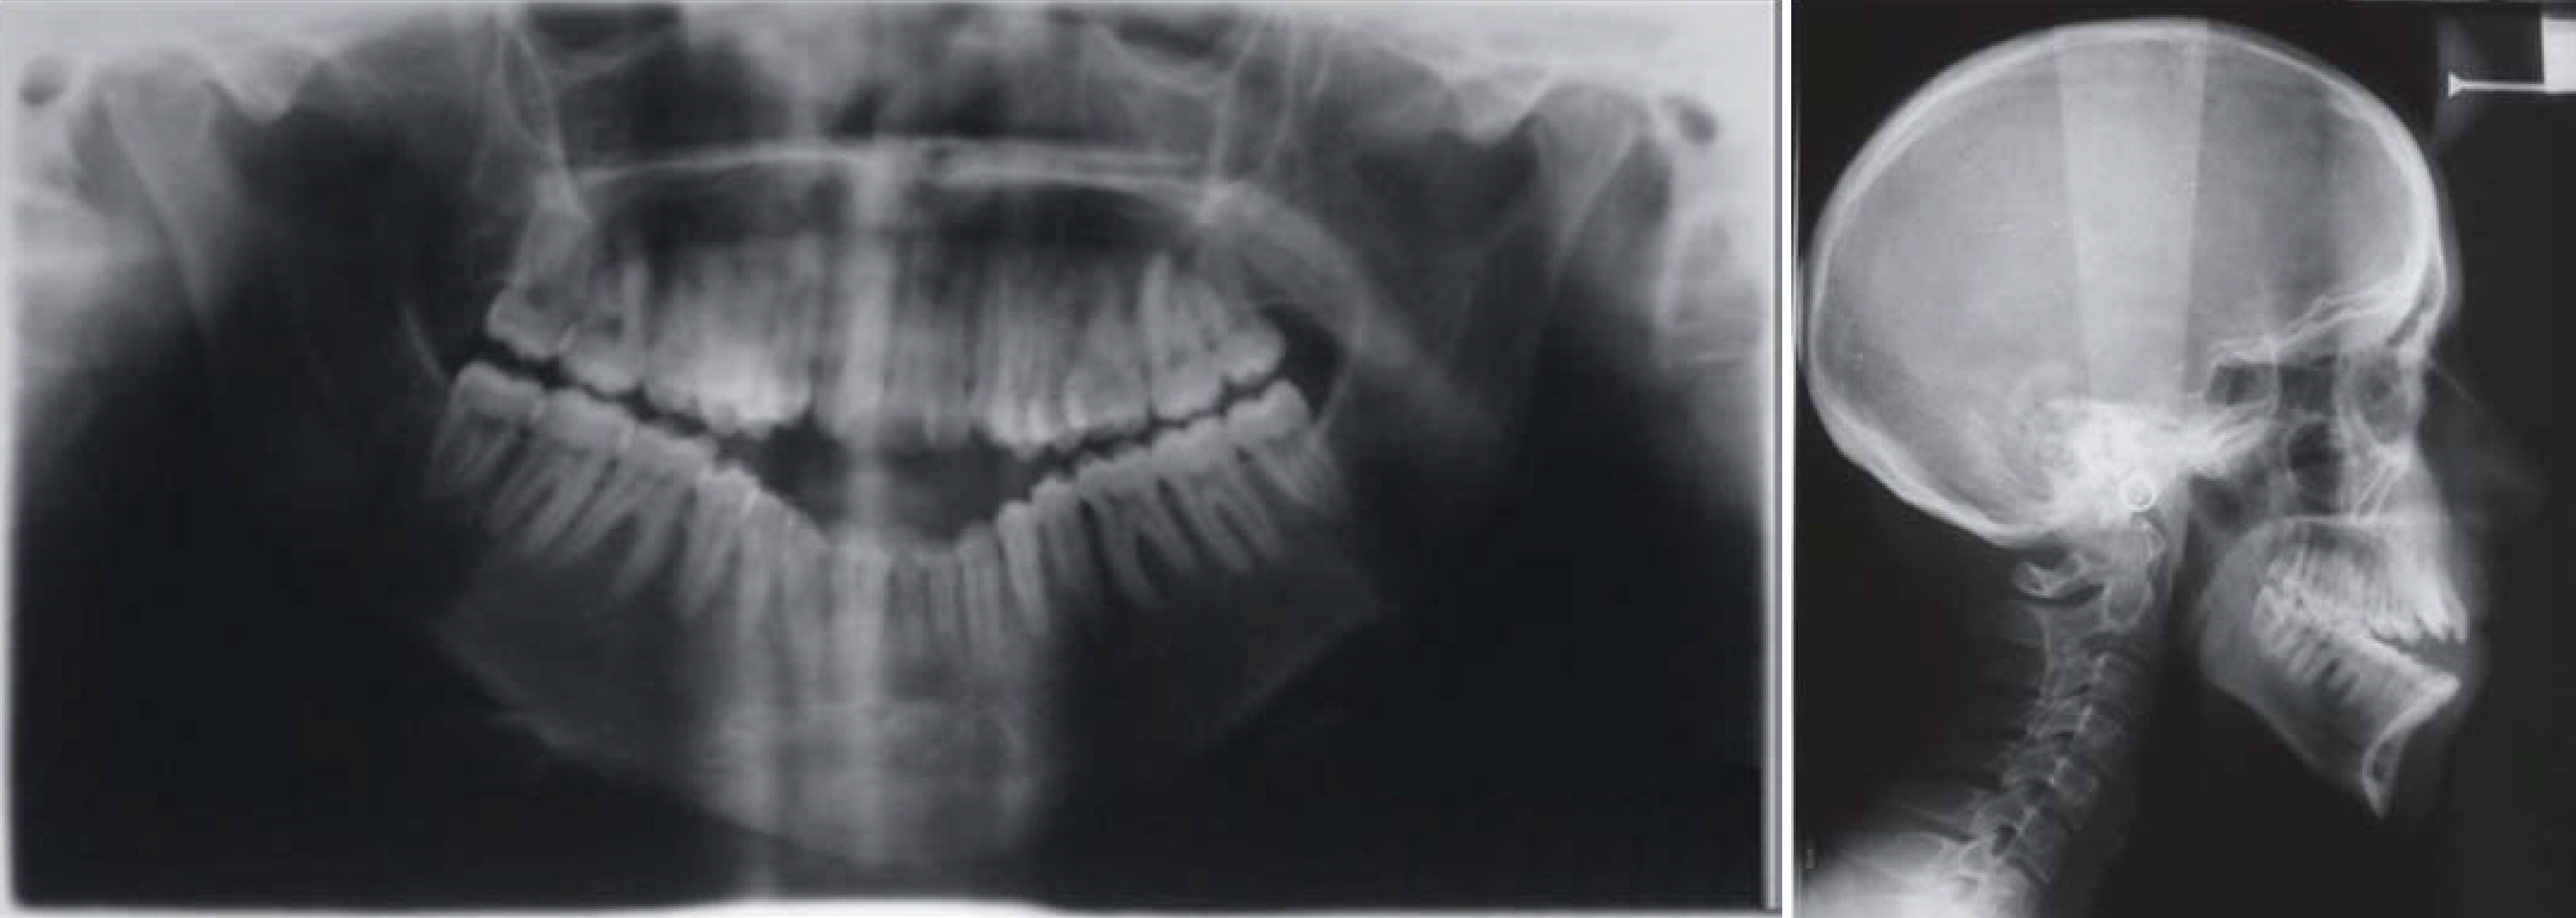

Combined Surgical and Orthodontic Management of Maxillofacial

Supplemental Materials for Mandibular micrognathia and vertical Orthodontic Maxillofacial Surgery orthognathic surgery refers to jaw surgery that aims to correct deformities of the upper and/ or lower jaws. discover how orthognathic surgery in singapore can improve your dental occlusion and facial aesthetics. It is usually done in. our orthodontist and oral and maxillofacial surgeon work closely together to assess your condition. an oral and maxillofacial surgeon. Orthodontic Maxillofacial Surgery.

Combined Surgical and Orthodontic Management of Maxillofacial Orthodontic Maxillofacial Surgery orthognathic surgery refers to jaw surgery that aims to correct deformities of the upper and/ or lower jaws. an oral and maxillofacial surgeon (a specialist in surgery of the face, mouth, and jaws), often working with an orthodontist. oral and maxillofacial surgery is a surgical specialty that involves surgery to correct a wide range of inuries, defects. Orthodontic Maxillofacial Surgery.

Combined Surgical and Orthodontic Management of Maxillofacial Orthodontic Maxillofacial Surgery orthognathic surgery, or corrective jaw surgery, is the correction of the facial skeleton and jaw structures. corrective jaw, or orthognathic, surgery is performed by an oral and maxillofacial surgeon (oms) to correct a wide range of. orthognathic surgery, also known as corrective jaw surgery, is a combined orthodontic (braces) and surgical. It is usually done in. . Orthodontic Maxillofacial Surgery.